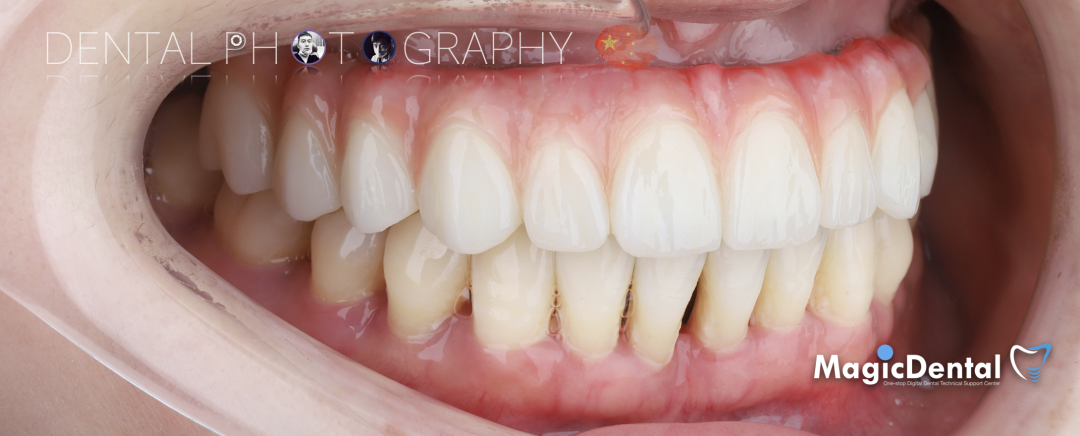

最终修复体制作完成

最终修复戴入口内后两周复查

术前术后对比